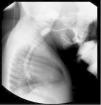

A male patient seen since he was 7 months of age at the pediatric gastroenterology service, with a history of upper respiratory symptoms since the first day, predominantly nocturnal nasopharyngeal reflux, recurrent broncho-obstructive episodes, episodes of apnea, cough during breastfeeding, sialorrhea, and poor secretion management. With complementary feeding, he presented with choking, the passage of food content through the nose, vomiting, and occasional regurgitation. At the first consultation, the patient’s anthropometric measurements were weight: 7.65 kg (–0.87 SD), height: 70 cm (0.08 SD), and weight-for-height: (–1.18 SD). Physical examination revealed no alterations. Due to clinical oropharyngeal dysphagia, an esophagogastroduodenoscopy (EGD) was performed that revealed a 60% reduction of the cervical esophageal lumen between C3 and C4 (Fig. 1), suggesting a cricopharyngeal spasm vs a vascular ring. In the EGD, a 60% reduction of the cricopharyngeal lumen was observed that impeded the passage of the endoscope. At 8 months of life, the first session of endoscopic dilation was carried out, improving the dysphagia and respiratory symptoms. Cricopharyngeal achalasia was suspected. High-resolution esophageal manometry, with a solid-state probe, using a 4.2 mm external probe and 36 sensors, showed an abnormal pressurization pattern in the cricopharyngeus muscle consistent with CA (Fig. 2). The patient was symptom-free up to 28 months of life, after which he presented with recurrence of the dysphagia. At present, the patient has required two endoscopic dilations, at 30 and 46 months. In the first dilation, an 8 mm balloon was employed and progressively advanced to 10 mm, 12 mm, and 15 mm. The patient currently has no dysphagia at 56 months of life, no new bronco-obstructive events, and weight gain is adequate.

The study in the initial approach is the EGD or videofluoroscopy swallowing study; they evaluate the passage of contrast medium or food through the pharynx and the signs of penetration and/or aspiration into the airway.5 Typical findings are filiform passage through the cervical esophagus, accumulation in the pharynx, nasal regurgitation or contrast medium aspiration, and posterior protrusion into the pharyngoesophageal junction at the C5-C6 level.6 Esophageal manometry is the confirmatory diagnostic method; it evaluates the opening pressures of the upper esophageal sphincter (UES).4,6 Elevated resting pressures of the UES and absence of its relaxation during swallowing, with panesophageal pressurization, have been described in CA, findings that were found in our patient (Fig. 2). Some authors suggest EGD as part of the routine study of CA and describe spasm in the esophageal introitus as characteristic.6 Our patient presented with all the alterations reported in the literature, in all the studies mentioned above.